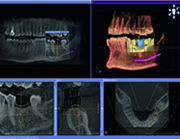

歯周病と歯科用CT歯周病により破壊された骨を歯科用CTで正確に分析することが出来ます。現状の骨の状態を把握することにより、歯の寿命を予測し、非常に予知性の高い治療を行うことが可能です。